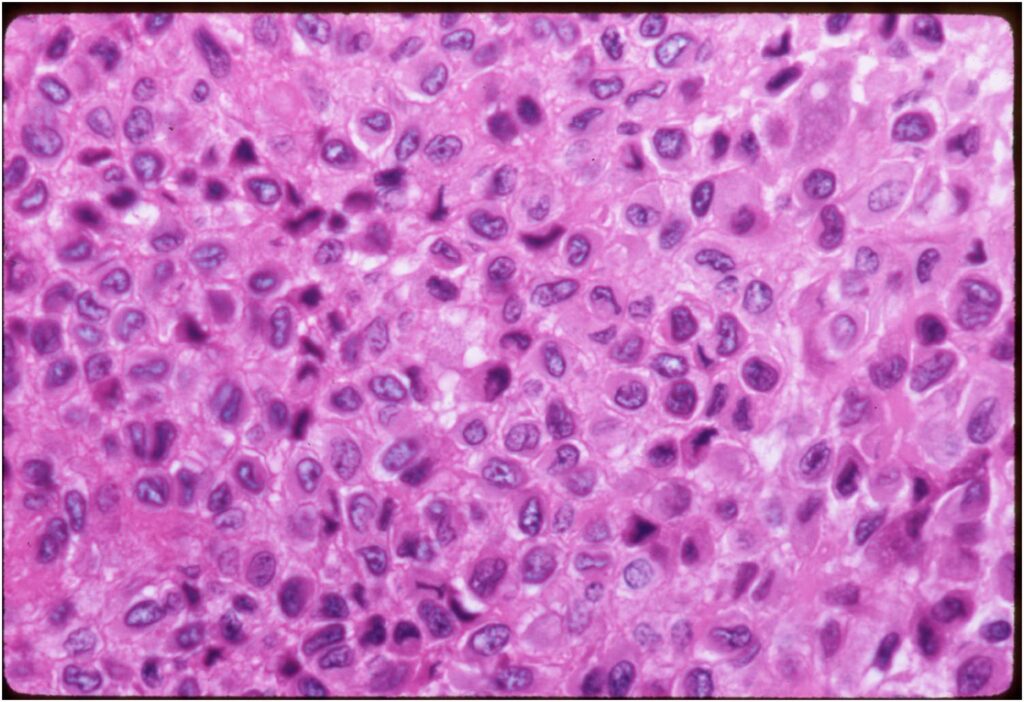

General Information Enchondroma is a benign indolent intramedullary hyaline cartilage neoplasm Accounts for 10% of all benign osseous tumors Limited growth, most lesions are less than 5 cm in maximal dimension Bones grow from a cartilaginous growth plate that...